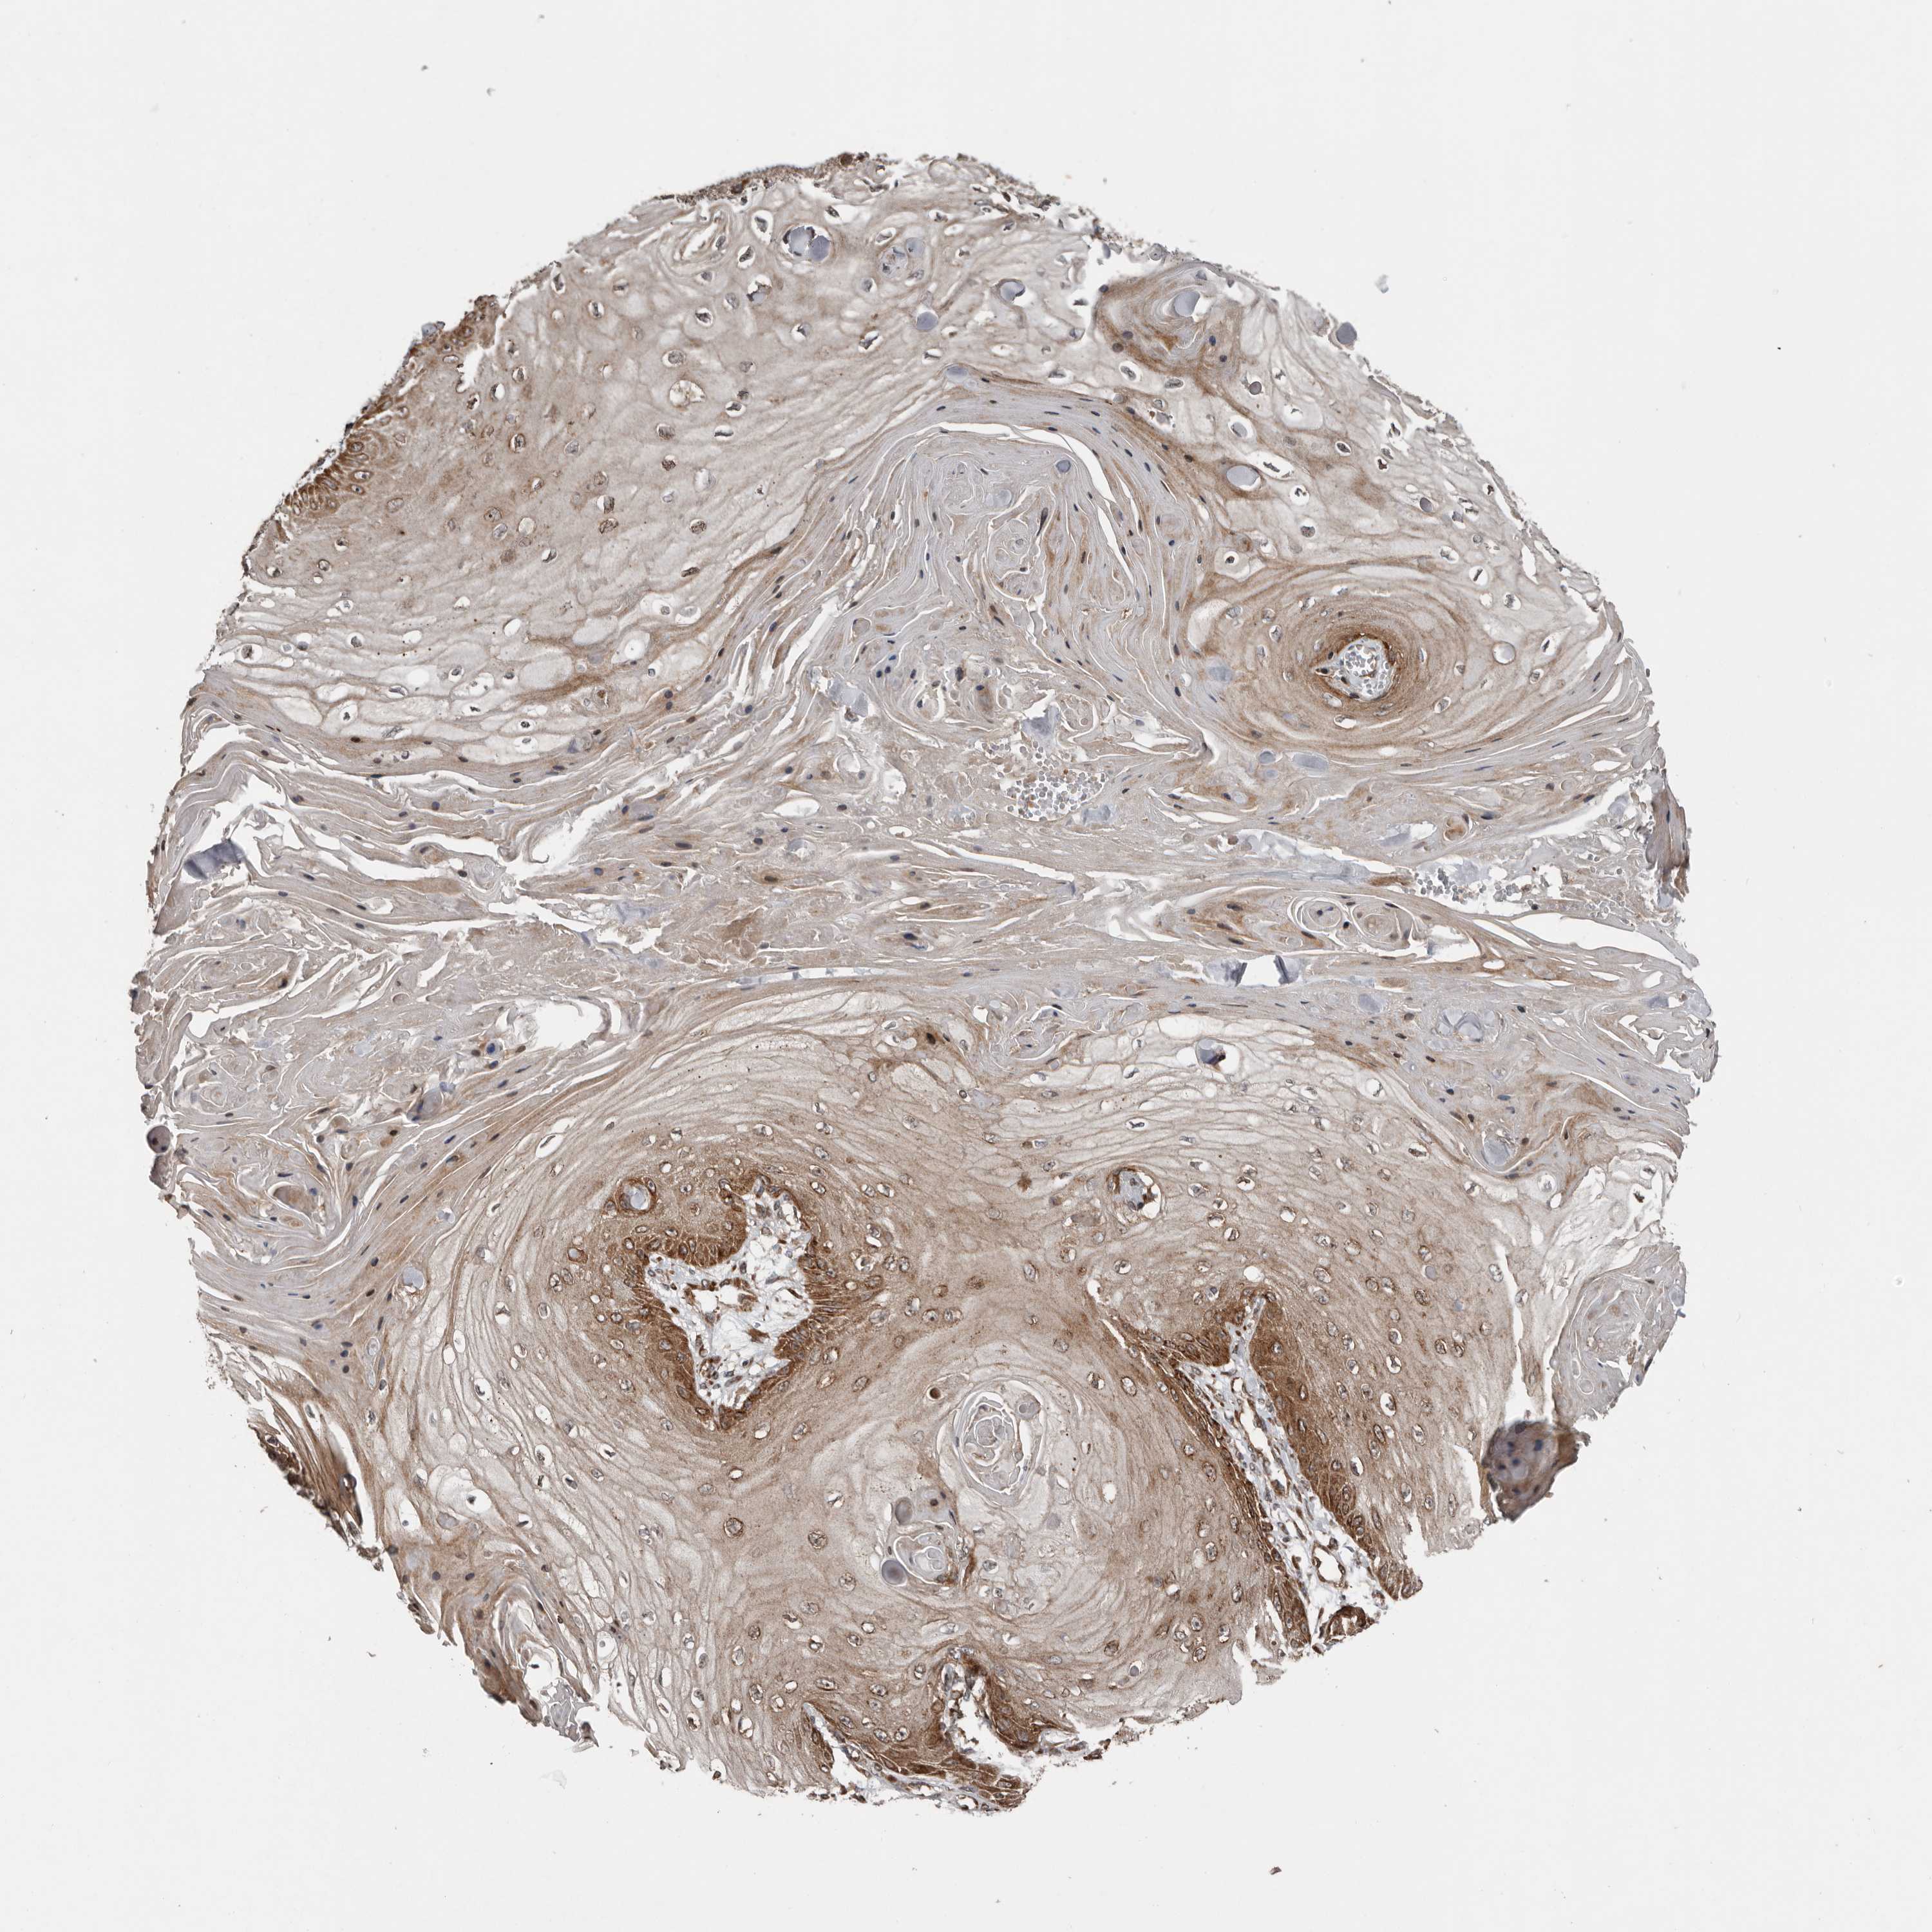

SKIN CANCER - Protein expressioni

A mouse-over function shows sample information and annotation data. Click on an image to view it in a full screen mode. Samples can be filtered based on level of antibody staining by selecting one or several of the following categories: high, medium, low and not detected. The assay and annotation is described here.

Each image is clickable and will lead to virtual microscopy that enables deeper exploration of all samples and also displays staining intensity scores, fraction scores and subcellular localization as well as patient and tissue information for each sample.

Antibody HPA028584

Squamous cell carcinoma, NOS